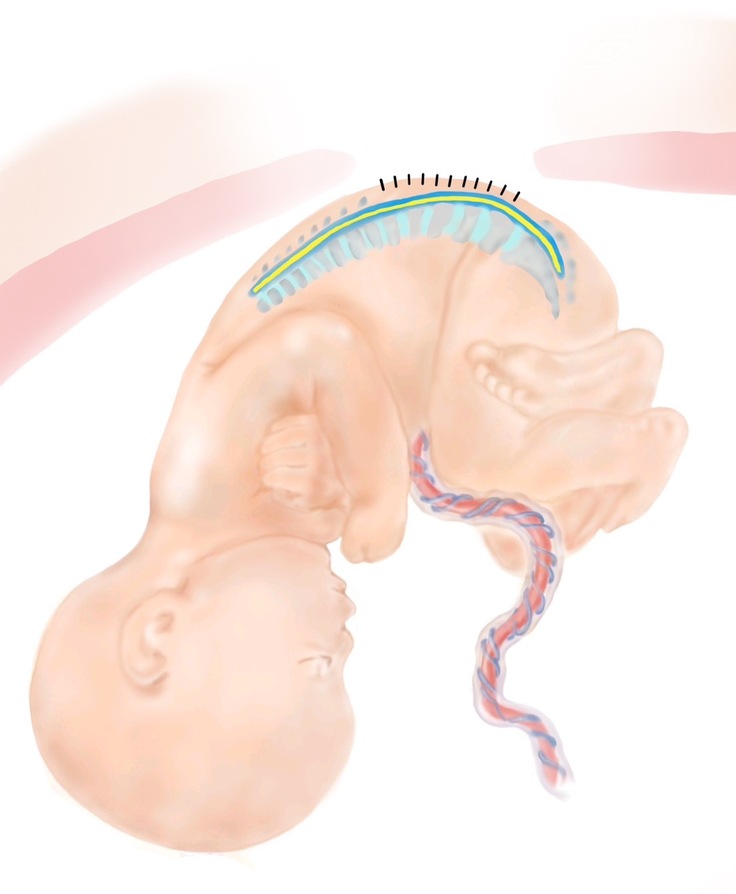

みなさん、お気づきだと思いますが、このプロジェクトの紹介ページには、たくさんのイラストを載せています。お腹の中で病気になっている赤ちゃんの絵なので、見る人に不安やこわさを与えないように、やさしいタッチで描いたイラストを掲載しています。

実は、このイラスト、私たちの仲間で、大阪大学の総合周産期母子医療センターで事務職員として働いているKさんが描いてくれたものなんです。見ていると穏やかになる落ち着いた絵ですよね。しかも、病気のことをできるだけ正確に表現したいので、一度描いてくれた絵を私たちと何度も見直して、正確に表現できるようになるまで根気強く描き直してくれてできたイラストたちなんです。大変思い入れのあるイラストたちです。

この場を借りて、Kさん、ありがとう。これからもよろしくお願いします。